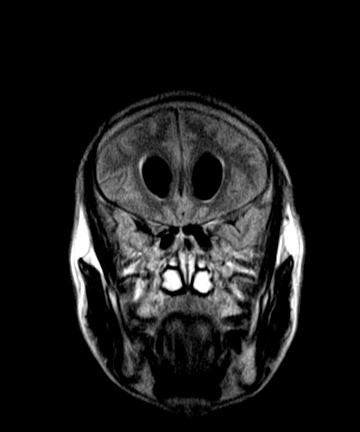

标题: MRI2064:少见病例。男性52,视力下降多年。 [打印本页]

标题: MRI2064:少见病例。男性52,视力下降多年。

四脑室区见混杂信号占位影,脑室系统扩张明显,临近结构显著受压称位,患者52岁,多考虑室管膜瘤可能性大

考虑第四脑室室管膜瘤并阻塞性脑积水。

考虑第四脑室室管膜瘤并梗阻性脑积水;部分性空蝶鞍;左侧上颌窦粘膜下囊肿。

考虑第四脑室室管膜瘤【血供丰富血管母细胞瘤可能】并梗阻性脑积水;部分性空蝶鞍;左侧上颌窦粘膜下囊肿。

比较典型的脉络丛乳头状瘤并脑积水,鉴别小脑蚓部血管母细胞瘤。